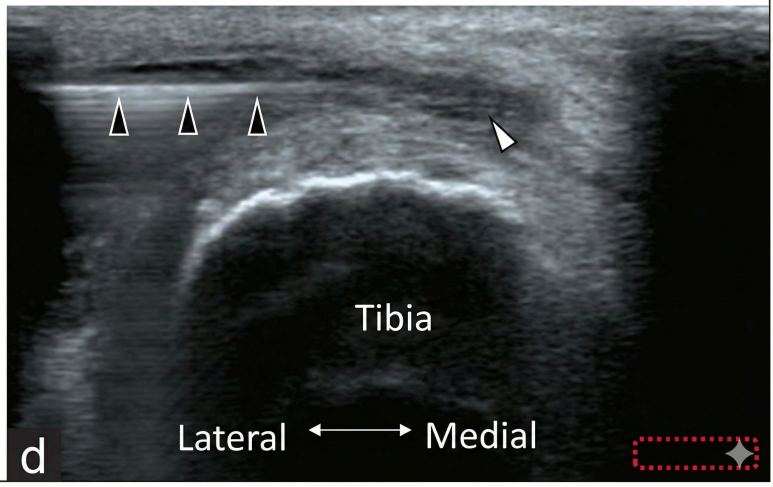

이 논문에서는

무릎 앞쪽이 붓고 아픈 환자를

초음파로 진단했습니다.

논문의 초음파 영상을 보면

피하층에 까맣게 물이 고여 있고

그 주변으로 혈류가 증가해

빨갛게 보이는 염증 소견이 확인됩니다.

그리고 여기서 중요한 핵심은

이 점액낭(물주머니)은통증 수용체가 아주 발달해 있어서,염증이 생기면 극심하게 아프다는 겁니다.